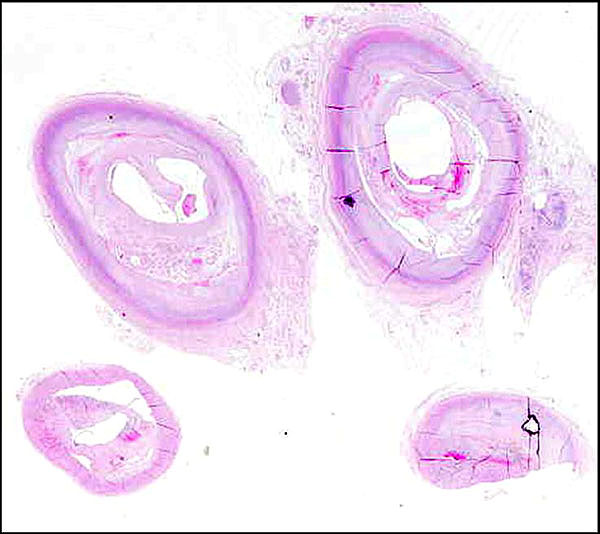

Placas de ateroma